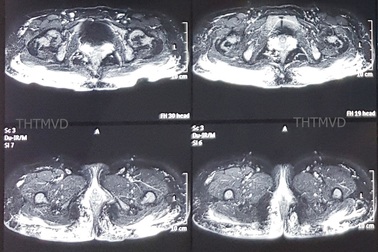

Vùng mông lổn nhổn hàng trăm u cục chỉ vì tiêm mỡ nhân tạo tại spaCô gái 25 tuổi nhập viện với vùng mông bị sưng nề với hàng trăm khối u siliconoma, nhiều vết thủng loét đã vỡ dò chảy mủ ra ngoài, đặc biệt là nhiễm một loại vi khuẩn đa kháng thuốc.